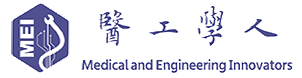

数字化智慧病理科建设全景图

来源:蛋壳研究院